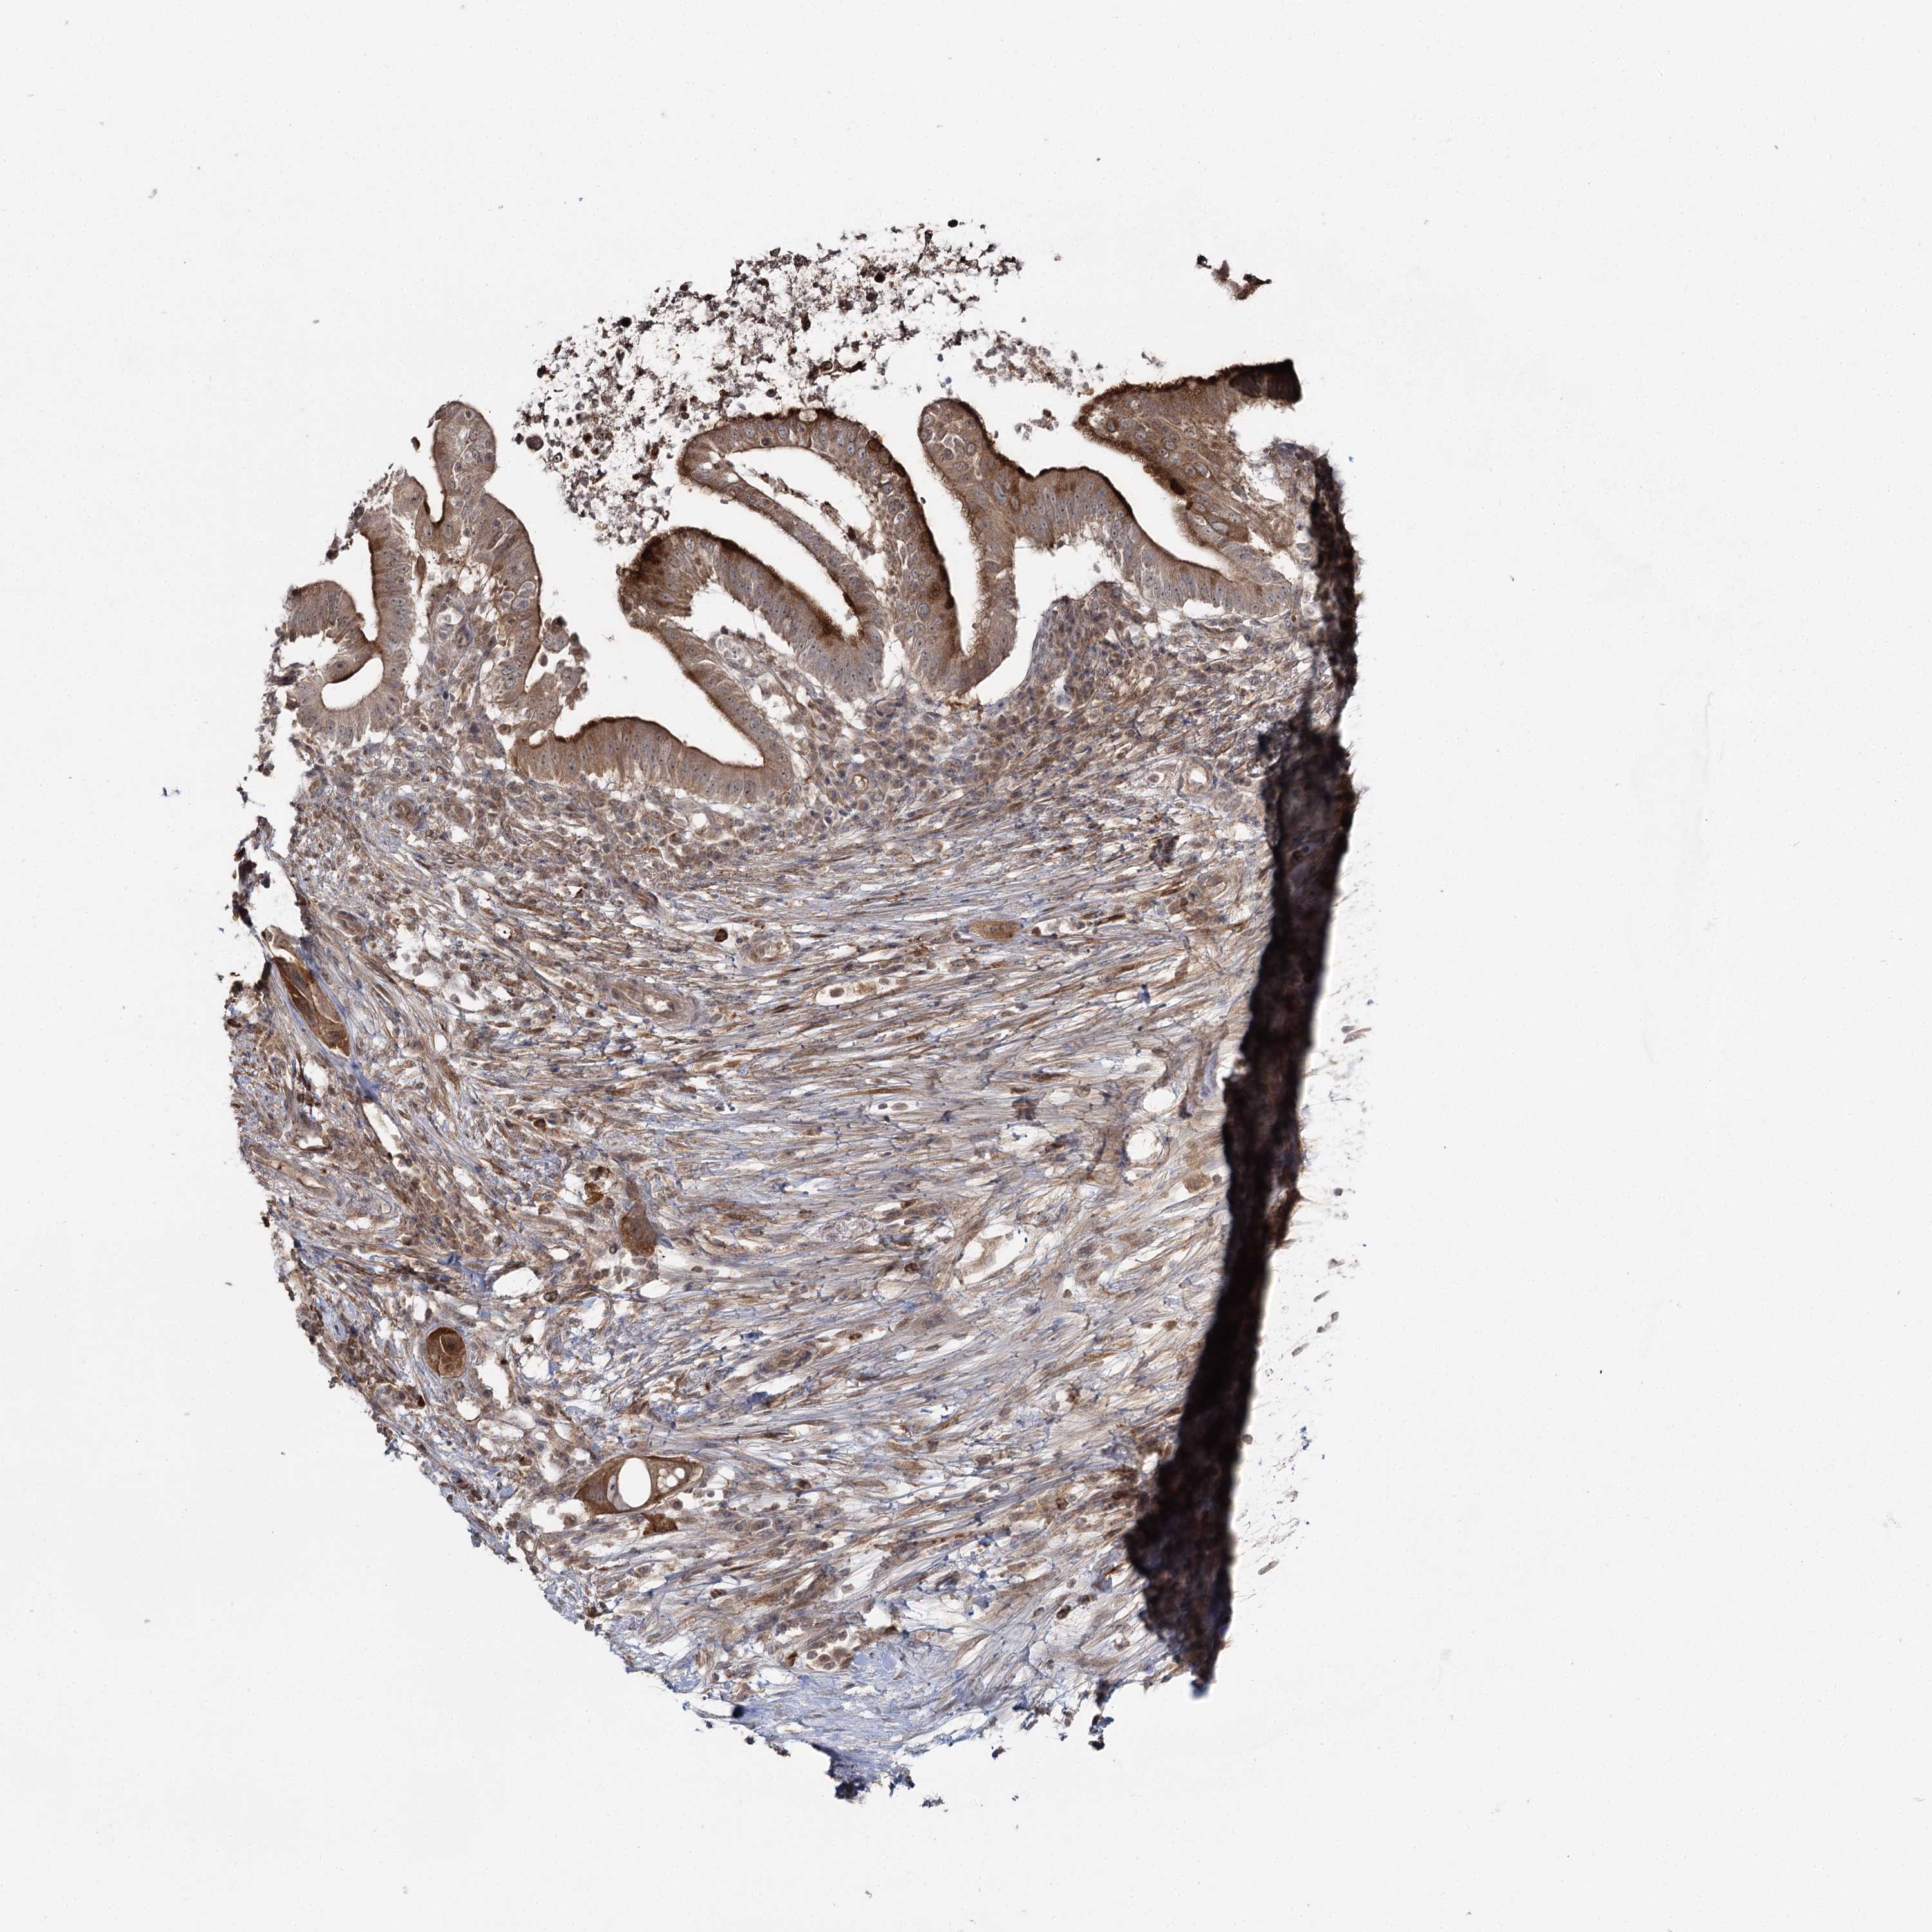

PANCREATIC CANCER - Protein expressioni

A mouse-over function shows sample information and annotation data. Click on an image to view it in a full screen mode. Samples can be filtered based on level of antibody staining by selecting one or several of the following categories: high, medium, low and not detected. The assay and annotation is described here.

Note that samples used for immunohistochemistry by the Human Protein Atlas do not correspond to samples in the TCGA dataset.

Antibody stainingi

Antibody staining in the annotated cell types in the current human tissue is reported as not detected, low, medium, or high, based on conventional immunohistochemistry profiling in selected tissues. This score is based on the combination of the staining intensity and fraction of stained cells.

Each image is clickable and will lead to virtual microscopy that enables deeper exploration of all samples and also displays staining intensity scores, fraction scores and subcellular localization as well as patient and tissue information for each sample.

Antibody HPA038084

Staining

High

Medium

Low

Not detected

Intensity

Strong

Moderate

Weak

Negative

Quantity

>75%

75%-25%

<25%

None

Location

Nuclear

Cytoplasmic/membranous

Cytoplasmic/membranous,nuclear

Adenocarcinoma, NOS